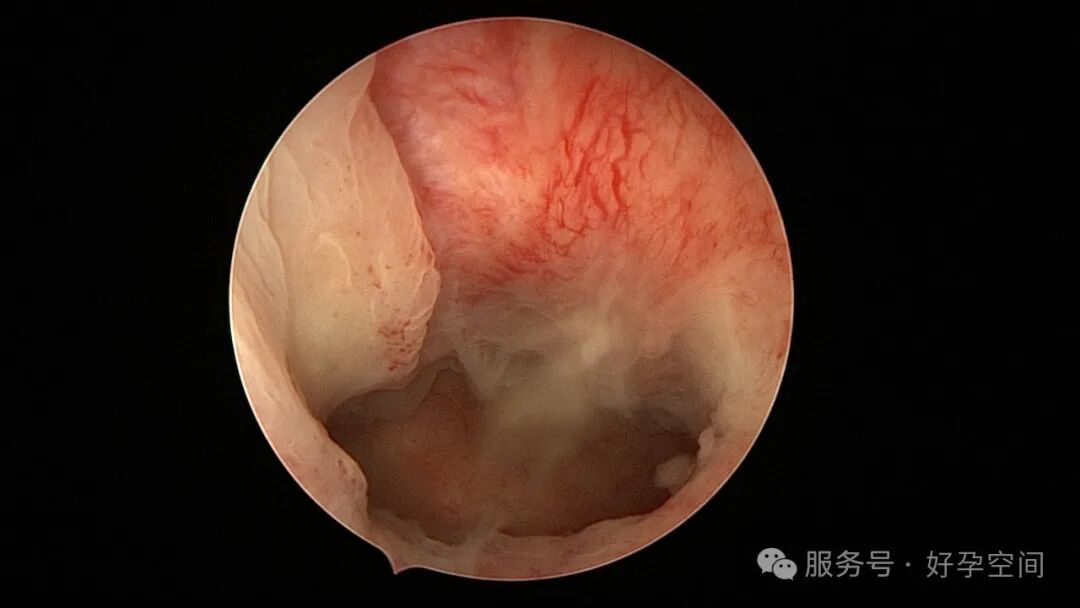

试管前宫腔镜检查